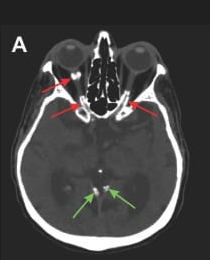

Bilateral Optic Nerve Sheath Calcifications (CT scan).

Diagnosis: Secondary Hyperparathyroidism with Orbital Calcification in CKD.

Certainty: Certain

Author: Dr usman Raza

Date Published: Mar 24, 2026

Disease Specialty: Nephrology

Image Type:

CT Scan